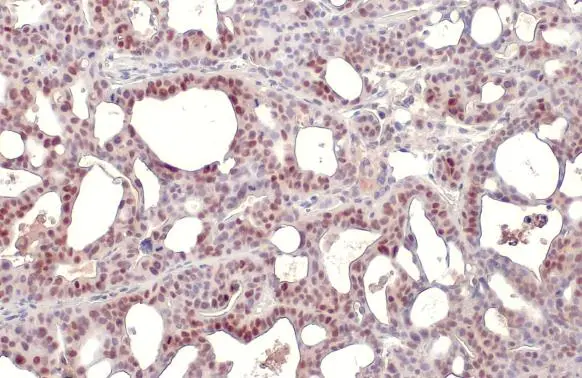

Anti-p53 antibody [DO1] used in IHC (Paraffin sections) (IHC-P). GTX70214

GTX70214 IHC-P Image

p53 antibody [DO1] detects p53 protein at nucleus by immunohistochemical analysis.

Sample: Paraffin-embedded human SW480 xenograft.

p53 stained by p53 antibody [DO1] (GTX70214) diluted at 1:100.

Antigen Retrieval: Citrate buffer, pH 6.0, 15 min

5 / 14